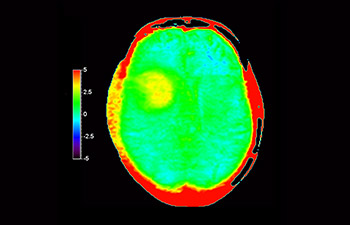

3D APT (Amide Proton Transfer) is a unique, contrast-free, brain MR imaging method addressing the need for more confident diagnosis in neuro oncology. 3D APT uses the presence of endogenous cellular proteins, to produce an MR signal that directly correlates with cell proliferation, a marker of tumoral activity. 3D APT can support trained medical professionals in differentiating low grade from high grade gliomas and, in differentiating tumor progression from treatment effect1.

3D T1w TFE 3D APT

Glioblastoma image

Brain with glioblastoma

with 3D APT

Glioblastoma recurrence

Brain imaging for glioblastoma recurrence